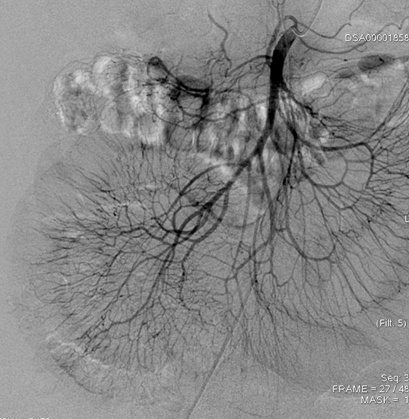

图1. 肠系膜动脉造影(DSA)

办好住院已经是1月13日下午四点了,介入科方淳主任及团队加班加点,当天晚上就为患者做了肠系膜动脉和静脉造影,结果没有发现大血管的问题,但是小血管充血、丰富,呈梳子样改变(称为“梳子征”,图1)。排除了肠系膜大血管的问题之后,高度怀疑肠系膜小血管炎可能,事不宜迟,赵家胜主任通过电话联系到风湿免疫科值夜班的王璇主治医生,王医生仔细询问了病史,了解到患者有过脱发和自发性流产的病史,结合本次肠道小血管炎的表现,高度怀疑系统性红斑狼疮引起的肠系膜血管炎。为了缓解患者的腹痛,挽救病人的生命,王璇医生基于对病情的判断,在化验结果尚未出来的情况下果断使用了糖皮质激素,第二天早上(1月14日)患者腹痛和恶心、呕吐即明显好转,患者胃口也开了,随后吃了点半流质,但下午又出现了腹痛和呕吐,这时化验结果也出来了(见图2),狼疮的标志性抗体-抗Sm抗体和ds-DNA抗体均阳性,证实了系统性红斑狼疮的诊断。赵主任和风湿免疫科汤建平主任共同查房后认为系统性红斑狼疮诊断明确,以急性腹痛起病,而且一发病就表现为狼疮危象的红斑狼疮少见,常规剂量激素疗效不佳,腹部CT结果显示肠壁水肿和胸腹水有进展(见图3、图4),需要立即进行大剂量激素冲击治疗。